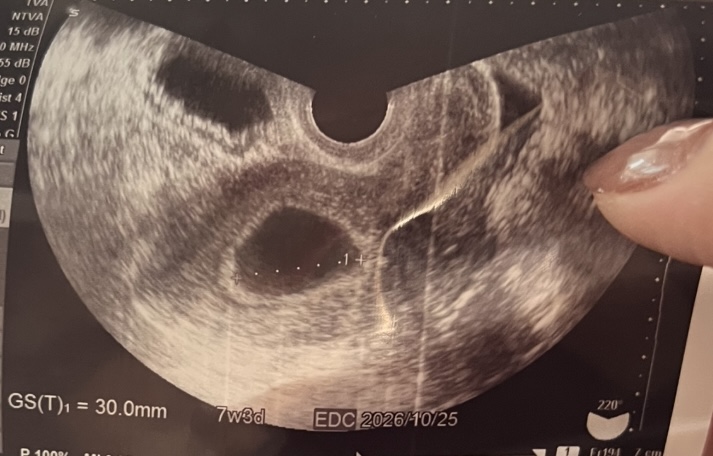

先日妊娠が分かり、最終月経日から数えて6w5dの今日産婦人科を受診しました。エコーを見てもらい胎嚢が30.0mmと7w3dに相当する大きさでしたが心拍は確認できないので2週間後に改めてきてくださいと言われました。先生には排卵がズレている可能性もあるから!と言われましたがズレていたとしてもタイミングを取ったのが1.2回しかなくそのどちらかになるので2.3日くらいしかズレていないと思います。こちらのエコー写真には赤ちゃんがいるようなものは写ってはいないでしょうか?(卵黄嚢など)胎嚢だけ大きく何も見えないのは不安です。また、胎嚢の他に左右にも袋が見えます。特に先生からは指摘はありませんが気になりました。

赤ちゃんの姿はなかったということで、お写真を拝見いたしましたが、袋だけのように思いました。

胎嚢の他に見られるものは一つは膀胱に当たるのではないかと思いました。

もう一つの方ははっきりとわからないのですが、子宮の中には胎嚢だけのように見えました。